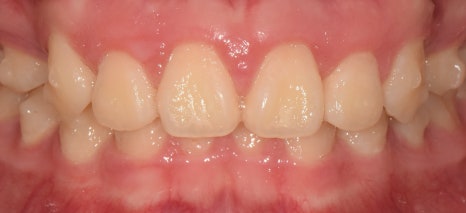

처음에는

치아가 보이지 않을 정도로

많이 튀어나왔지만,

턱이 뒤로 들어가면서

올바른 형태로 찾아갈 수 있었습니다.